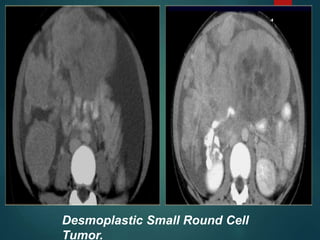

Desmoplastic Small Round Cell

Tumor…

• Rare malignancy of uncertain origin.

• Young men with a mean age of 19 years.

• Consider this diagnosis if we see something

that looks like peritoneal carcinomatosis in a

young man that has no history of a primary

malignancy.

• It is a very aggressive tumor with a poor

prognosis.

Tumor.

Desmoplastic Small RoundCell Tumor… • Rare malignancy of uncertain origin. • Young men with a mean age of 19 years. • Consider this diagnosis if we see something that looks like peritoneal carcinomatosis in a young man that has no history of a primary malignancy. • It is a very aggressive tumor with a poor prognosis.